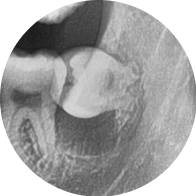

파노라마 및 소형 엑스레이 촬영 결과,

하악 좌측 제3대구치 아래 6mm 이상의

방사선 투과성 병소(검게 보이는 낭종 조직)가 확인되었고,

치아 낭종으로 의심되었습니다.